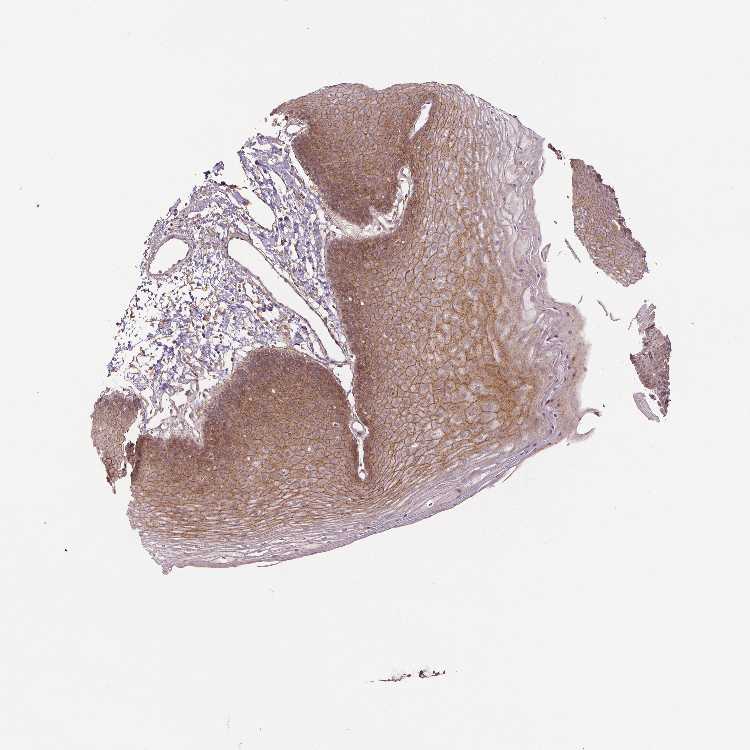

SKIN 2 - Antibody stainingi

Antibody staining in the annotated cell types in the current human tissue is reported as not detected, low, medium, or high, based on conventional immunohistochemistry profiling in selected tissues. This score is based on the combination of the staining intensity and fraction of stained cells.

Each image is clickable and will lead to virtual microscopy that enables deeper exploration of all samples and also displays staining intensity scores, fraction scores and subcellular localization as well as patient and tissue information for each sample.

Antibody CAB034350

Epidermal cells Medium